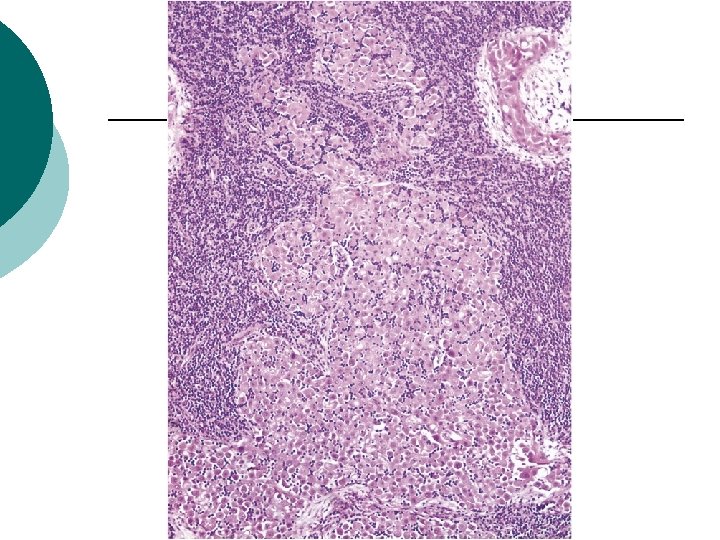

Intraglandular pattern

Intraglandular Pattern ¡ ¡ ¡ 21/31 3 cases consisted entirely of the intraglandular pattern, one of which formed nodular aggregates with associated stromal reaction. 3 patients with intraglandular LNI had stromal microinvasion in the primary ovarian tumor and 3 had micropapillary architecture. All patients with intraglandular LNI had intraperitoneal implants (3 invasive and 18 noninvasive). Follow-up information : 11 NED and 3 AWD at 11, 38, and 230 months Disease-free survival versus LNI without this pattern : 79% and 71% respectively